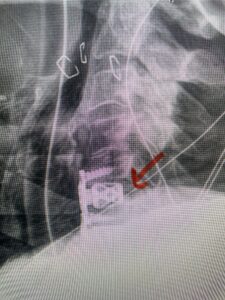

This 61-year-old female with a history of severe osteoporosis and a prior history of a laminectomy from l2-S1 with an L5-S1 instrumented fusion, presents with progressive low back pain and right lower extremity radiculopathy. MRI revealed a grade 1 L2-3 spondylolisthesis with severe stenosis mainly from severe right L2-3 facet joint hypertrophy which was compressing the right L3 descending nerve root. (Fig. 1). She had failed conservative management consisting of physical therapy and pain management with epidurals. She underwent an L1-3 revision laminectomy where we had to dissect a plane underneath the inferior aspect of the L2 lamina. We performed an instrumented fusion at L2-3 with special hydroxyapatite-coated screws to improve fixation to surrounding bone given here severe osteoporosis (Fig. 2) This worked out well and the patient had an uneventful recovery with relief of her leg pain.

Fig: 2a: AP and lateral intraoperative fluoroscopic images demonstrating good placement of L2-3 pedicle screws